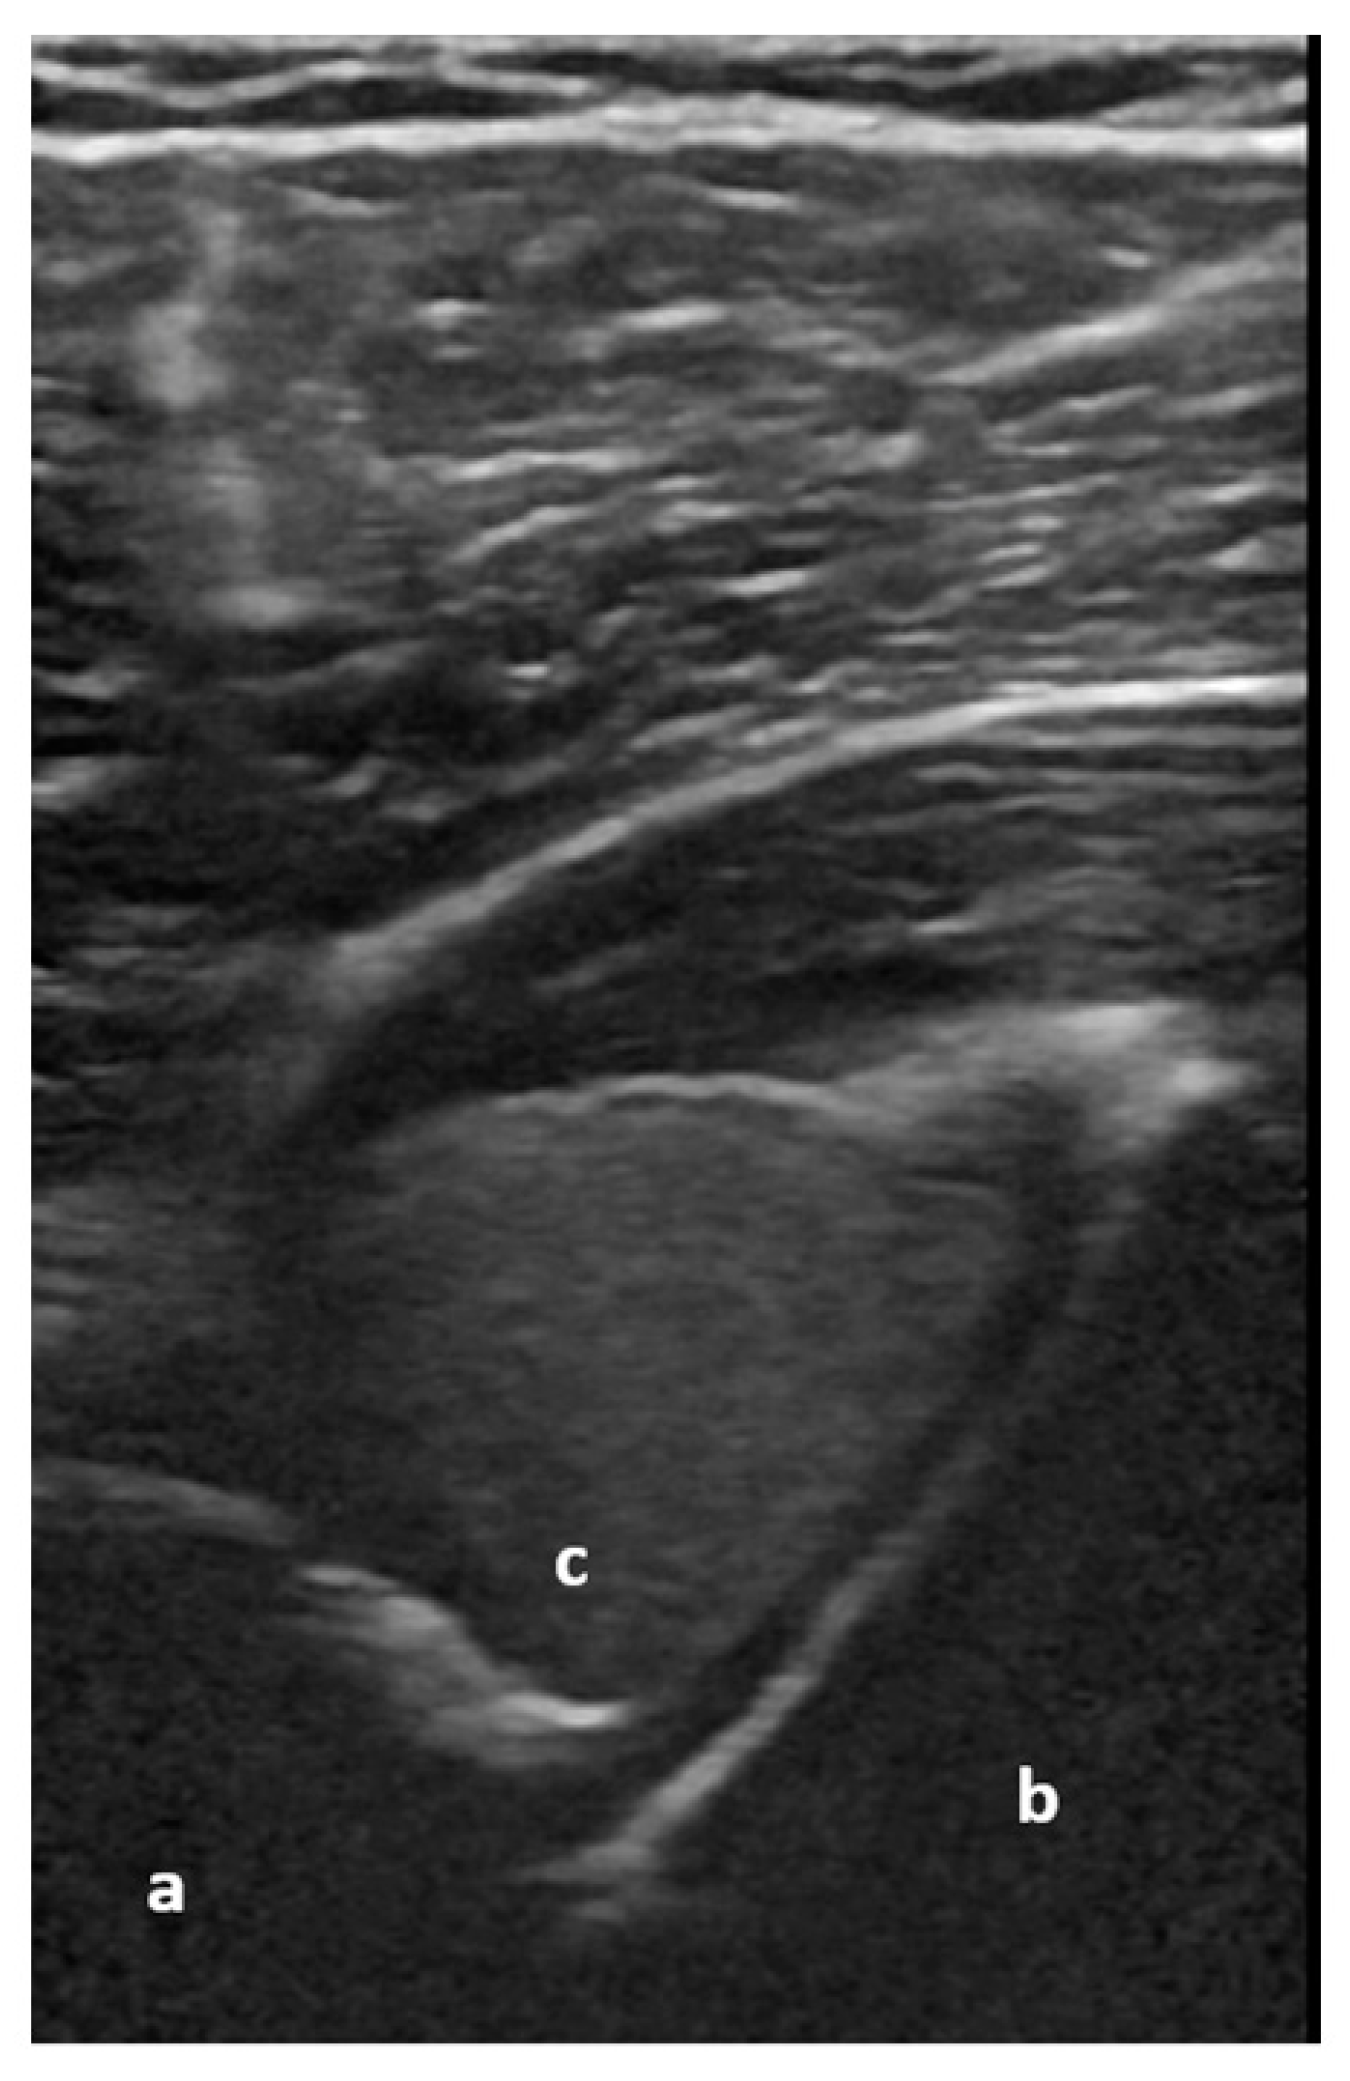

Figure 4.

Non-displaced major tuberosity fracture: lateral sagittal view at the level of the major tuberosity with corticalis interruptions (a) and chimney sign (b). Image courtesy of J. Osterwalder.

Figure 5.

Dorsal transverse view of an anteriorly dislocated humeral head (a), glenoid (b), and hemarthrosis (c). Image courtesy of J. Osterwalder.